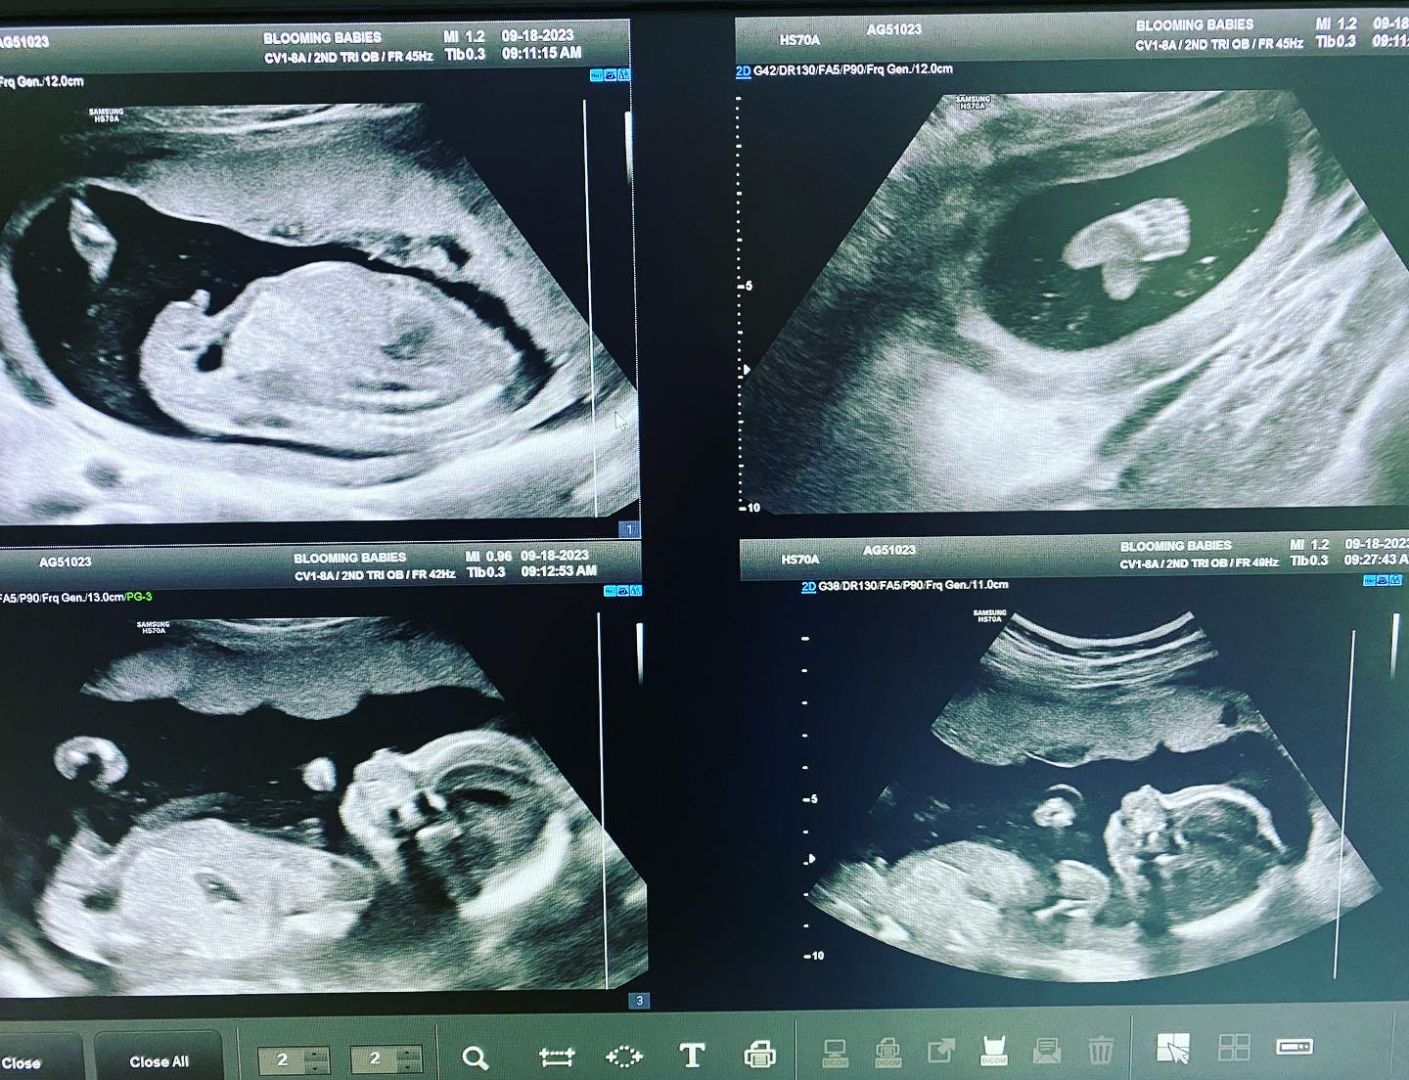

I will never forget walking out the doors of the OB/Gyn office one day in 2021. I occasionally work for Obstetricians and perinatologists in the area if needed. After a long day of scanning around 14 pregnant patients, I caught myself smiling as I got into my car to drive to the hospital where I work full time. On this particular day, I was able to show husbands and wives their baby’s heart beat for the very first time, or show cute profile pictures of their baby or tell them their baby has lots of hair or long eyelashes! I could go on and on! Seeing the joy on the parents to be faces brings me so much unexplainable joy! My heart feels like it could explode! I had a couple patients that day that came in to have their very first early ultrasound. Unfortunately, for those patients, the news was grim. I had to explain that there was no heart motion seen. As difficult as this is to explain to excited parents to be, I was able to comfort them, answer questions to the best of my ability, offer them pictures and give advice; as I, myself have experienced the loss of babies. As I left that day smiling, I thought to myself, I could do this all day for free! Then the lightbulb went on! Should I just start my own little side business? The thought of owning my own business scared the shit outta me. I’m not gonna lie. Haha! Well, my researching began! I started out looking up other private ultrasound places in and around the Orange County area. Much to my surprise, most of the people running these businesses and the techs performing the ultrasounds were not registered, licensed sonographers! They did not go to qualified schools, they did not have any experience working with Drs, clinics or at hospitals. To me, this is a disservice in the community. Our pregnant moms-to-be deserve better! And so it began………

I was assigned to intern at Hoag Hospital Newport Beach starting in 2009. Talk about a huge learning curve! I had no background in the medical field whatsoever. I was suddenly working alongside physicians, radiologists, nurses, therapists, ob/gyns, surgeons, etc, etc. All while learning how to hold and manipulate these foreign objects of many shapes and sizes, called ultrasound probes! It’s not what most people think. Most people assume an ultrasound tech looks at babies all day and just moves a probe around. That is not it at all! We have to be able to “tell a story” per se and be able to convince radiologists of our findings,know how to create a good image no matter the body part! We have to scan testicles, abdomens, thyroids, baby brains, arm and leg veins, pelvics and more! And it does not stop there. We have to be able to write up our impression of the exam, give measurements and explain everything we see or don’t see. It takes several years before a radiologist will fully trust our work. We get questioned a lot, have to rescan a lot. It can be VERY nerve wracking the first few years. 2 years in to my career, I was hired to work part time for a perinatologist (high risk OB). I had very little experience, but the Dr was willing to train me. This is where I learned SO much and my scanning skills really improved. I quickly realized how much I loved the interaction with these patients and their families. I made a special bond with a lot of them and have been able to watch their baby’s grow up. 🙂 I scanned lots of twins and triplets and I have been able to help my co-workers at the hospital with their OB exams. One of the biggest compliments I received as an ultrasound tech is when the head radiologist in our department said, “If I were pregnant, I would want you to scan me.” That was a huge compliment!! I have continued to have other radiologists ask me questions and ask my opinion when it comes to OB ultrasounds. It is extremely flattering!

I have been told that I am different than most ultrasound techs in that I engage with the patient, their significant other and I will include their kids if there are any. I will explain everything I am doing and answer as many questions as allowed. I try my best to make it an enjoyable, unforgettable moment and bonding with the baby. My goal in having my own little private ultrasound studio is to keep it very simple. No other techs other than myself scanning, no waiting rooms and no crossing paths with any other clients.